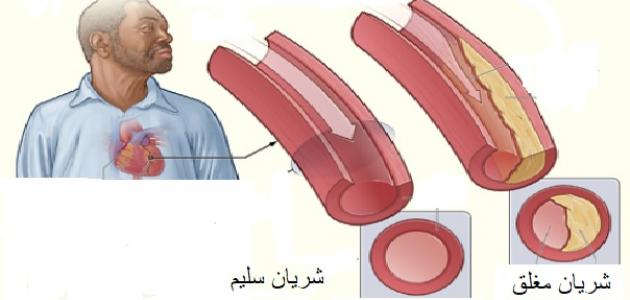

تحدث الإصابة بأمراض الشريان التاجي والأوعية الدموية نتيجة المعاناة من تصلّب الشرايين (بالإنجليزية: Atherosclerosis) في الغالب، ويُعدّ داء الشريان التاجيّ أكثر أنواع أمراض القلب شيوعاً، وهو المسبّب الرئيسيّ للنوبات القلبيّة والذبحة الصدريّة (بالإنجليزية: Angina)، إذ يكون مصحوباً بتضيّق أو انسداد الشرايين التاجيّة المغذية لعضلة القلب، أمّا بالنسبة لأمراض الأوعية الدمويّة ذات الصلة فهي الأمراض التي تصيب أنواع أخرى من الشرايين والأوردة وتؤدي إلى ضعف التروية الدمويّة وتؤثر في وظائف القلب.[٣]

تحدث الإصابة بالنوبة القلبيّة أو ما يُعرَف أيضاً باحتشاء عضلة القلب (بالإنجليزية: Myocardial infarction) نتيجة الانخفاض الشديد في سرعة تدفّق الدم في أحد الشرايين التاجيّة المغذية لعضلة القلب، أو انسداده بشكلٍ مفاجئ، وفي الغالب تكون الإصابة بالنوبة القلبيّة ناجمة عن تشكّل الخثرة الدمويّة في أحد الشرايين التاجيّة المتضيّقة نتيجة المعاناة من تصلّب الشرايين.[٧]

وفي هذا السياق يُشار إلى أنّ تصلّب الشرايين هو التضيّق والتصلّب الحاصل في الشرايين نتيجة تراكم الدهون التي تُسمى الصفيحات الدهنيّة في جدرانها، ممّا يؤدي إلى إعاقة تدفّق الدم خلالها وضعف التروية الدمويّة للعضو المُغذّى بهذا الشريان، بالإضافة إلى ارتفاع خطر تشكّل الخثرات الدمويّة التي قد تؤدي بدورها إلى انسداد الشريان، وقد يكون الشريان مسؤولًا عن تغذية الدماغ أو القلب، ويشار إلى أنّ مرض تصلّب الشرايين قد لا يكون مصحوباً بأيّة أعراض واضحة، ممّا يؤدي إلى تطوّر المرض دون علم الشخص المصاب، وقد يؤدي إلى المعاناة من بعض المضاعفات الصحيّة الخطيرة في المراحل المتقدّمة من المرض مثل الجلطة الدماغيّة والنوبة القلبيّة، وتجدر الإشارة إلى إمكانيّة الحدّ من خطر الإصابة بمرض تصلّب الشرايين بشكلٍ كبير من خلال اتّباع أسلوب حياة صحيّ، والوقاية من تطوّر المضاعفات الصحيّة في حال حدوثه من خلال الالتزام بالخطة العلاجيّة التي يصفها الطبيب.[٨]